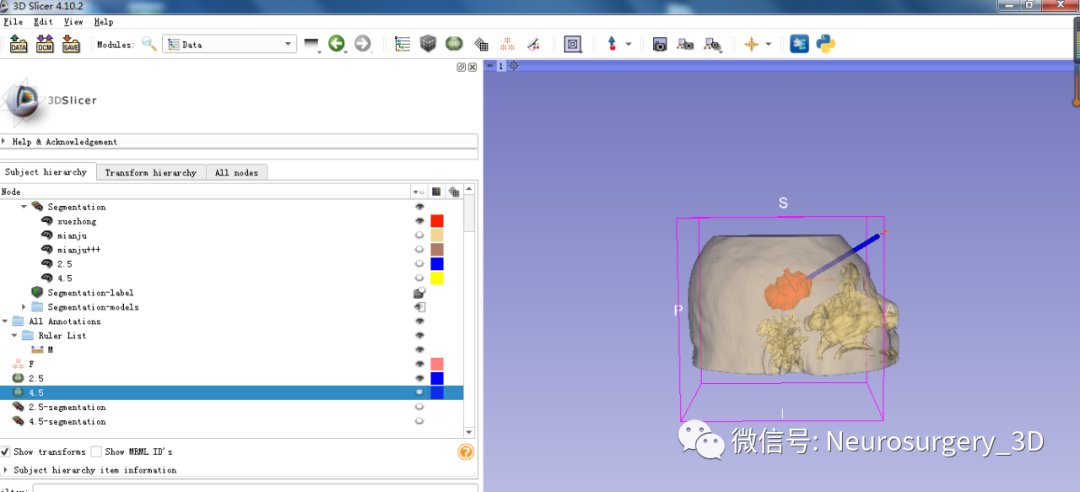

1、同阈值分割法建立血肿,应用阈值分割法三维重建头颅原始模型

2、可透视化显示颅内血肿形态

3、利用Logical operators逻辑运算模块复制头颅原始模型并扩大。

4、再次利用Logical operators逻辑运算模块,运算后重建出面具三维模型

运算后结果

放大后不同视角观察

1、利用Ruler测量出穿刺血肿靶点至穿刺外口的距离,并设计出穿刺路径顺血肿长轴走形在血肿中心(并非如下图所示所有穿刺路径均与矢状面平行、请注意穿刺深度),避开颅内重要结构如额窦、上矢状窦等。

入颅点避开了额窦、上矢状窦

透视化血肿状态下显示穿刺路径走形在血肿中心